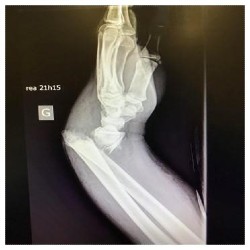

Fracture ouverte du poignet (radiographie en latéral).

Les traumatismes des membres supérieurs et inférieurs sont non vitaux. Cependant, il serait faux de croire qu’ils sont de moindre importance. Selon la gravité des lésions, une fracture peut mener à une section des vaisseaux et ainsi provoquer une multitude de visites en salle d’opération.